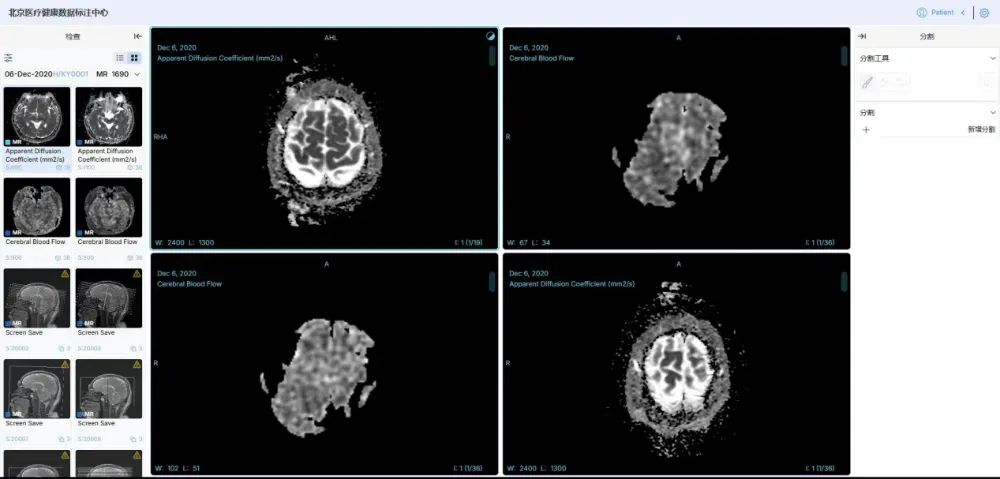

规模大、维度全、安全可信的高质量数据集。中国联通联合国内多家顶尖医疗机构,构建了覆盖影像、诊疗、药品等全维度的高质量数据集,其中,数据集总规模达 100TB,胸部CT影像数据集标注2万余例,肺结核辅助诊断模型准确率超95%;耳部CT影像数据集标注5000余例,听觉障碍识别准确率达95%;肾脏病慢病管理数据集整合1万例患者全周期数据,风险预警模型准确率突破95%;药品说明书数据集涵盖58000份药品信息,实现用药风险智能解析与动态评估。

在数据治理与管理方面,中国联通依托北京市全民言息平台,构建医疗健康行业可信空间,制定数据脱敏规范,运用数据沙箱和隐私计算双引擎处理数据,确保“原始数据不出域、数据可用不可见”。建立11项数据治理全流程运营标准,通过多维度举措保障数据质量与安全。例如,在胸部CT影像数据标注中,采用双盲标注和专家抽样审核,确保标注一致性评估结果超95%,准确性达98%以上。

高效、准确的系列医疗专科智能体。基于该高质量数据集,中国联通研发了一系列医疗专科智能体。基于胸部CT影像的肺结核疾病筛查与诊断模型智能体,准确率超 95%,可实现分钟级快速检测;肾脏病慢病管理干预模型智能体、耳部疾病辅助诊断模型智能体,助力医务人员提高诊断效率及诊疗方案准确性;药品全生命周期智能评估模型智能体,为药品研发、监管等提供全链条数据支撑。